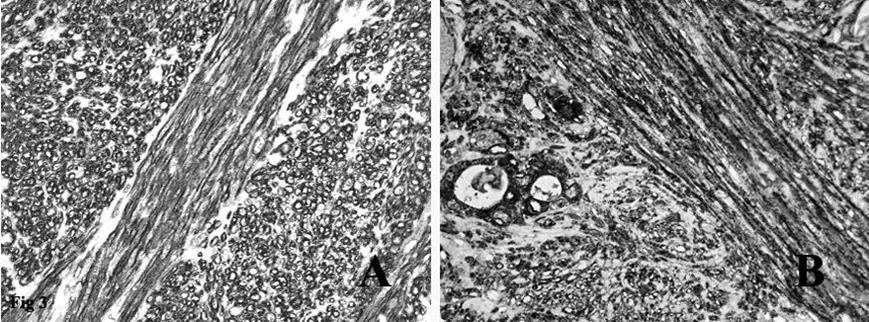

Figure 3.A. Immunohistochemical stain on the fascicles of tumor cells intersecting each other at right angles was strongly positive for smooth muscle actin. B. Immunohistochemical stain on the spindle tumor cells and on the residual thyroid follicles was positive for EMA.

Immunohistochemistry showed that the tumor spindle cells were strongly immunoreactive for vimentin, that is expressed by mesenchymal cells, actin HHF35, actin 1A4 (Figure 3A) and desmin, that are useful markers for the identification of smooth muscle cells. Finally, the spindle cells were positive for EMA (Figure 3B), a representative marker of epithelial cells.